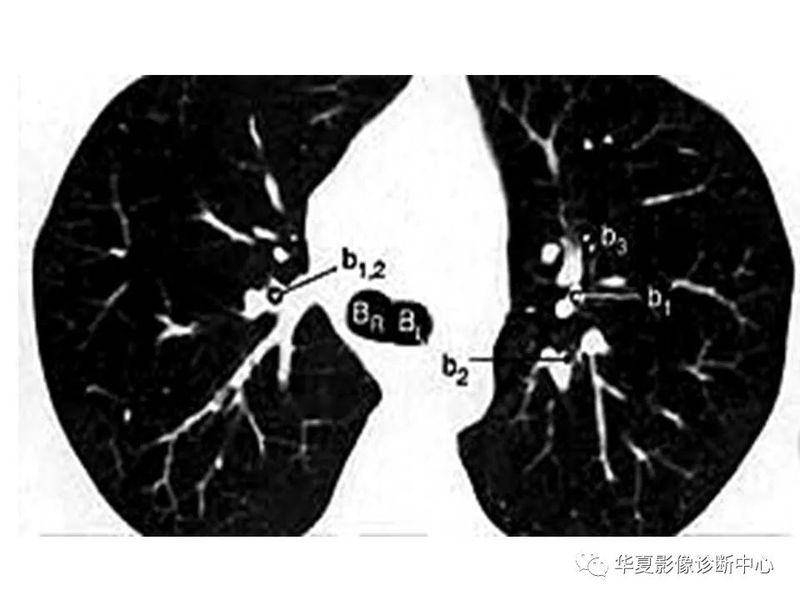

干货 | 汇总胸部CT读片扫盲知识,看懂胸部CT不再难